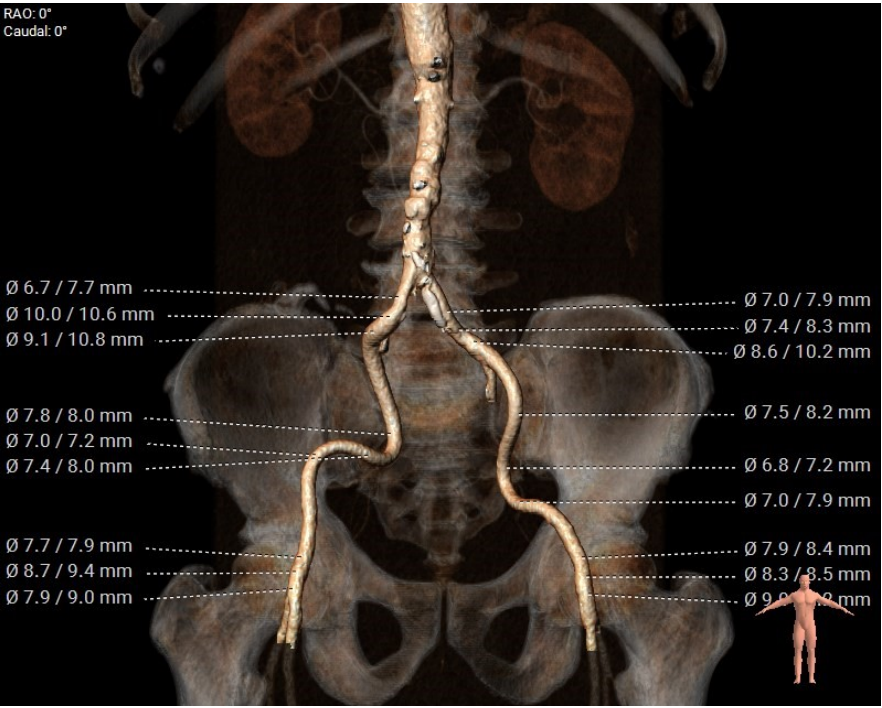

入路情况

手术策略采用右侧股动脉为主入路,全麻配合食道超声进行。根据瓣环测量数据,初步确定选择Evolut PRO 29mm瓣膜。是否需要针对Type0型二叶瓣采用downsize策略,团队进行了详尽探讨,决定先行20mm球囊扩张,根据球囊形态和瓣周漏情况决定最终选型。

5.左右髂总存在斑块、钙化。